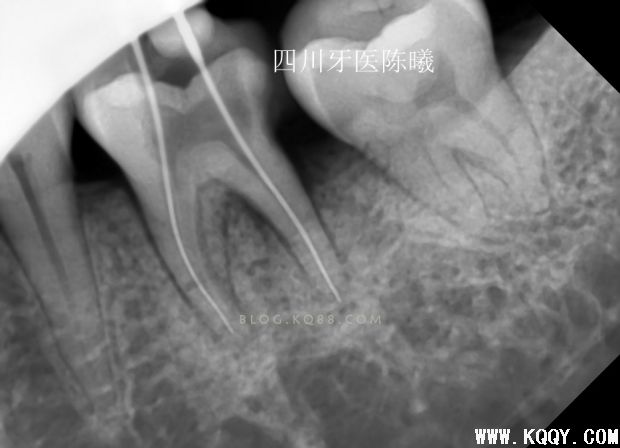

上次根管预备的测长片,当时为了做好就已经在预备后照了试尖片!可惜还是没有料到充填会有这么麻烦!

试尖后发现远颊主尖选择错误,由于是在预备的时候,所以也没有继续试,只是在病人收费票据上写清了个牙根情况!告知患者复诊时带来!(看到这您会问为什么不用病例,因为选择上班的地方都没有写小病例给病人的习惯,所以我也没有写,但是经过这个病例,在考虑以后根管治疗的病人都应该给病人一个病历本了!因为这个问题,成了造成后面问题的原因之一)

今天复诊的时候问病人收费票据,病人说忘带了,我让护士查了下上次的病例,自己也没有看,护士告诉我说扩到F1

没多想,准备拍片试尖了

试尖完发现近中稍欠,远中颊根部到位,于是用20#25#K挫稍微挫了下根尖3分之1,远颊根挫时病人告知有疼痛,依然没有重视,在冲洗的时候发现少许没有去除干净的氢氧化钙糊剂从根管内溢出,又是一个问题,这下觉得应该到位了,那就充填吧,于是用试尖的牙胶尖号数充填,结果如下